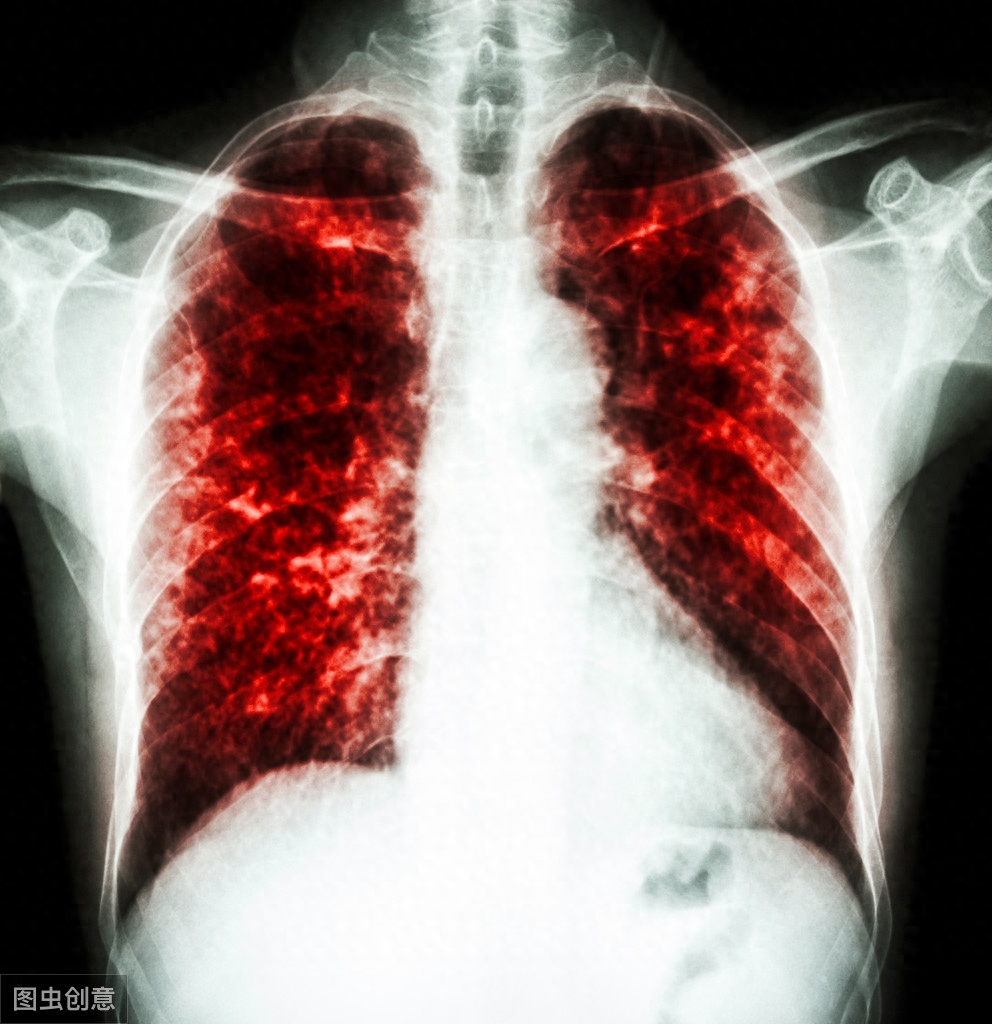

谈到肺癌,根据国际医学杂志《柳叶刀》近期发表的一篇关于中国人死亡原因排名的论文,肺癌居然排到了中国人死亡原因排行榜的第三的位置,这让很多肺癌患者不寒而栗。

除了肺癌本身的严重性以外,对于普通家庭来说,高额的治疗费也是压在他们身上的一座大山。在中国“看病难,看病贵”一直是社会持续关注的热点,对于肿瘤患者来说,他们需要长期治疗,不仅心理压力大,而且经济负担也是十分沉重的。这种情况正在被“4+7”政策打破。